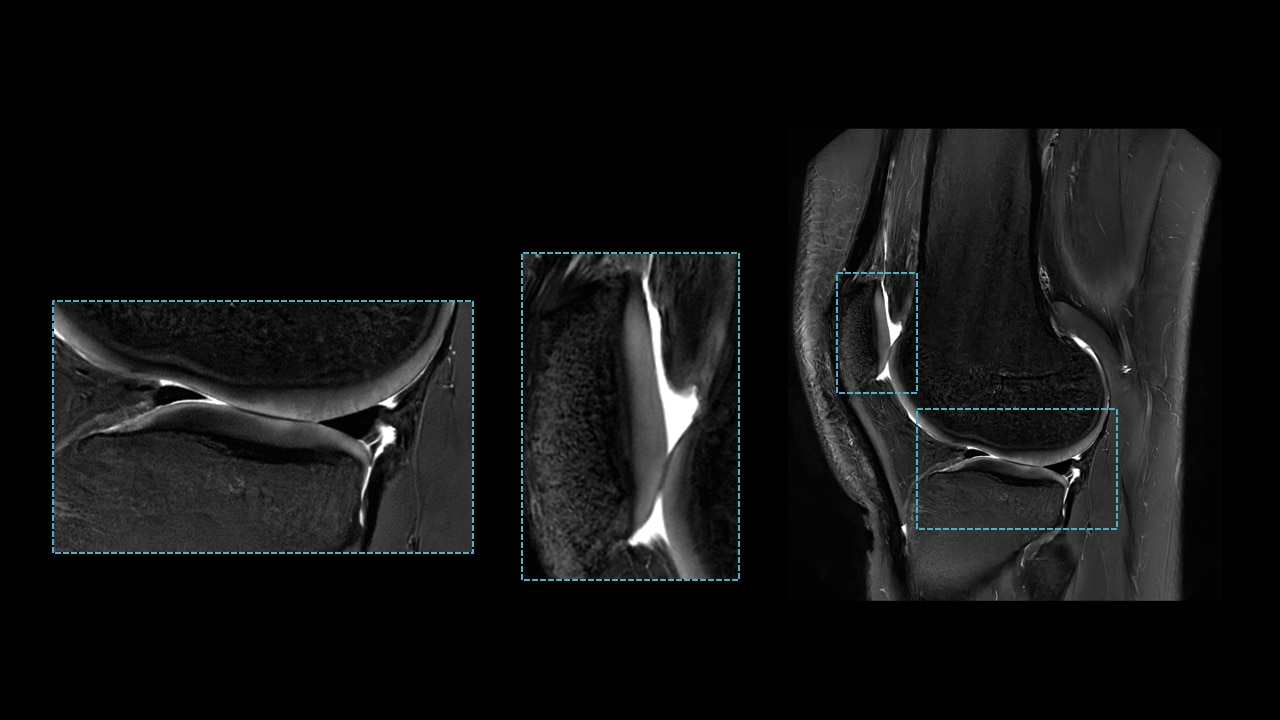

Diagnostic-quality images

Consistent images for challenging patients and difficult-to-image anatomies

Generate consistently good, diagnostic-quality images even for challenging patients and difficult-to-image anatomies.

PROPELLER uses a radial k-space filling pattern that is inherently less sensitive to motion such as CSF and blood flow, breathing, patient tremor, or voluntary movements. The oversampling of the k-space center yields increased signal-to-noise ratio (SNR) and high tissue contrast. Scan time is the same as conventional techniques, and PROPELLER allows free-breathing acquisition.